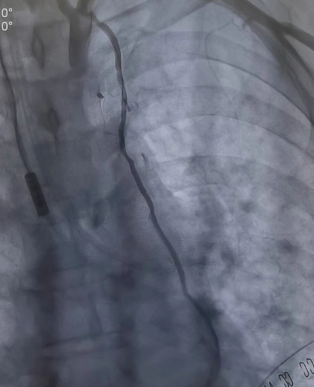

將兩者結(jié)合的手術(shù)方式就是雜交技術(shù)即“一站式微創(chuàng)”手術(shù)。手術(shù)先在左側(cè)胸壁做一個5-7厘米切口,進(jìn)行左胸廓內(nèi)動脈-左前降支(LIMA-LDA)架橋。接著進(jìn)行冠脈造影,檢查LIMA-LDA橋血管通暢度。同時在冠脈其他狹窄部位放入冠脈支架。

同期進(jìn)行冠脈放支架(檢查LIMA橋血管通暢)